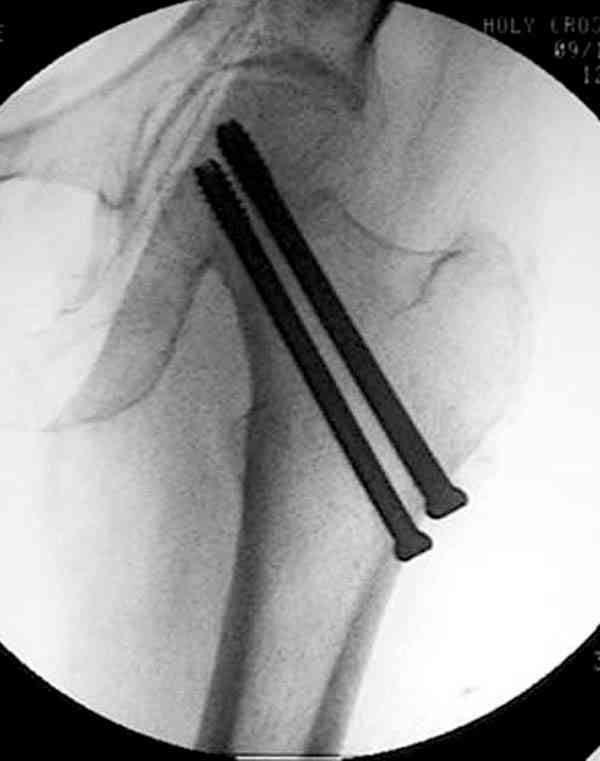

На Московской конференции в ноябре была продемонстрирована удивительная методика профилактического армирования шейки бедра у пациенток с остеопорозом и переломом контрлатеральной шейки в анамнезе.Странно, но дискуссии это сообщение не вызвало.Кто что думает об этом?

Спасибо, Антон. Я автор того сообщения по профилактическому армированию шейки бедренной кости, которое прозвучало на конференции, посвященной 50-летию создания АО. Мне тоже хотелось услышать вопросы по теме. Мы травматологи-ортопеды в первую очередь хирурги, а не терапевты. Почему в вопросе профилактики и лечения остеопороза мы ограничиваемся только консервативными методами лечения? Как можно практически научить больного не получать травмы, когда немало случаев возникновения переломов даже в постели. Первоначально идея армирования ШБК многих, при ком я озвучивал ее, шокировала, затем возникала дискуссия и большинство поддерживали эту идею. Мне бы очень хотелось развернуть дискуссию на странице этого сайта.

Кликните для загрузки файла P3230006.JPG

54KB (56062 bytes)

Уважаемый Антон! У меня было всего три клинических наблюдения, снимки были продемонстрированы на московской конференции. Количества этих снимков хватило для подачи заявки, а затем и получения патента на изобретение. В свое время РОСПАТЕНТ потребовал подтверждения методики клиническими наблюдениями. У одной из больных действительно произошла повторная травма, и произошел подвертельный перелом на стороне армированной шейки бедренной кости (см. снимки). Это подтвердило основную идею изобретения - была сохранена и головка, и армированная шейка бедренной кости. Но тут не обошлось безпроблем. Анестезиологи отказались давать наркоз, а провести остеосинтез под м/а пластиной и винтом DHS не согласилась больная. Дальнейшее лечение скелетным вытяжением. На контр. Рентгенограмме через 2 месяца признаки формирования костной мозоли. Повторных обращений двух других пациентов не было. Для более детальных исследований и выводов необходимо значительно большее количество клинических наблюдений. Такие исследования могли быть проведены в условиях клиник медуниверситета. Напомню, я работаю в травмотделении провинциальной городской больницы. Насчет экспертов страховых компаний, так пусть они выскажут свое мнение. Армирование кости - это плановые операции по желанию больного, какие здесь могут быть противоречия? На армирование все больные, к моему удивлению, согласились довольно легко и сразу, поэтому остеосинтез и армирование были проведены в течение одной операции. С уважением А.М.